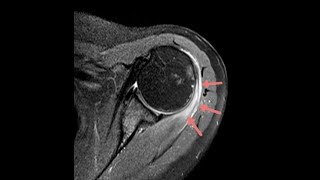

Flu vaccine tendinitis of shoulder video

Flu vaccine tendinitis of shoulder

Flu vaccine tendinitis of shoulder